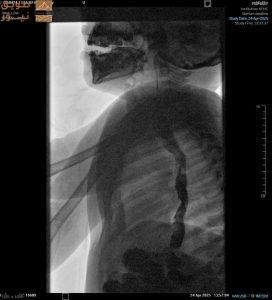

عبّر الدكتور عبد العزيز الحمود، رئيس قسم الأشعة في مستشفى صحة الافتراضي التابع لوزارة الصحة، عن فخره بنجاح البرنامج، قائلاً: “الابتكار هو حجر الزاوية في تحول الرعاية الصحية. وقد شكّل الانضمام إلى برنامج بناء القدرات الابتكارية لشركة سيمنز هيلثينيرز تجربة مميزة أكدت على قوة الابتكار والتعاون في تطوير تقديم الرعاية في المستقبل. هذه التجربة ترسخ من التزامنا بالتعاون مع شركة سيمنز هيلثينيرز لبناء الخبرات المحلية في الابتكار وريادة الأعمال والتسويق التجاري، وتحديد ومعالجة التحديات الكبرى في الرعاية الصحية، وتحسين التعاون بين المؤسسات.”